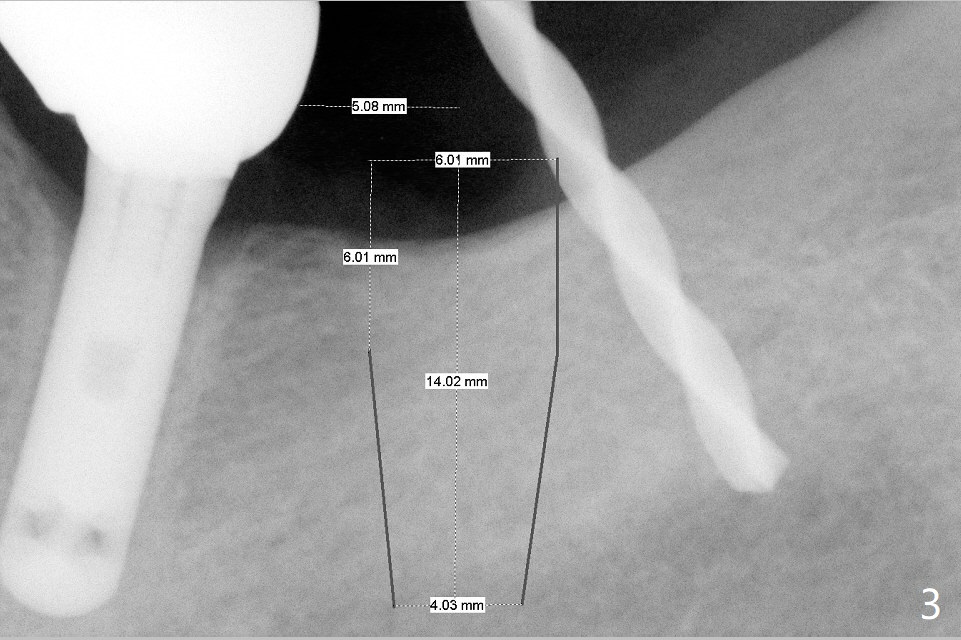

A 69-year-old man needs an implant at #18 (Fig.1,2 CT (sagittal and coronal sections)). In spite of use of surgical stent, the trajectory is not ideal (Fig.3-5). The following day the implant is removed with bone graft (Fig.6). In the 2nd placement, the trajectory is adjusted in each step (Fig.7-9 arrows) with long term stability (Fig.10,11).